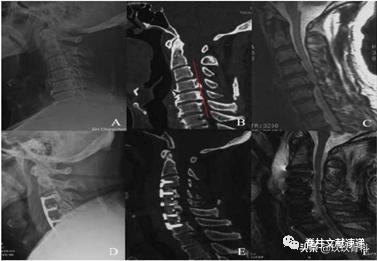

手术操作步骤(下图):A-D为矢状面观,E-J为轴面观。A切除椎体前面骨赘和椎间盘,B切除椎体前部,C椎间融合器植入,钉板预固定受累节段,并椎体两侧截骨开槽,D提拉,E术前OPLL状态,F切除椎体前部,G一侧开槽,H钉板预固定,I另一侧开槽,J提拉。

文章认为ACAF能够更好的恢复脊髓形态和脊柱序列,得到更好的JOA评分改善。文中病例: